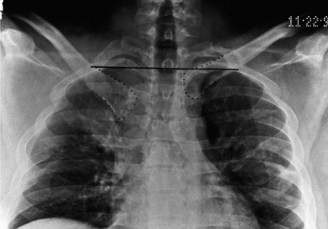

Standard radiography includes an anteroposterior view of the chest and a Serendipity view. The Serendipity view is obtained with the patient supine and the x-ray beam angled 40 degrees cephalad, centered on the manubrium. This view allows for comparison of the bilateral medial clavicles. In an anterior dislocation, the affected clavicle will appear superior to the uninjured side. In a posterior dislocation, the affected clavicle will appear inferior.

Despite the utility of the Serendipity view, computed tomography is the gold standard for evaluating sternoclavicular joint pathology. A CT scan of the chest with intravenous contrast should be obtained for all suspected posterior dislocations. Axial, coronal, and sagittal reconstructions clearly delineate the direction of displacement, the presence of physeal fractures in younger patients, and the relationship of the medial clavicle to the retrosternal vascular and aerodigestive structures. A CT angiogram is strongly recommended to rule out intimal tears, pseudoaneurysms, or direct compression of the great vessels.